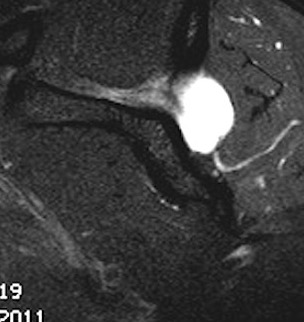

Posterior labral tears + cyst

www.boneschool.com/posterior-labral-cysts-suprascapular-nerve-compression